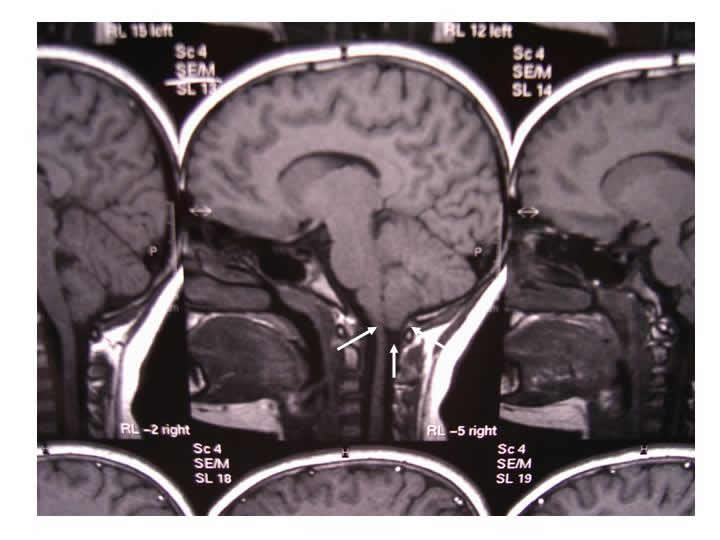

Caso clinico: C.L. di anni 10, di sesso femminile e di razza bianca, nasce a termine con parto eutocico. Nulla all'anamnesi familiare e fisiologica. La ragazza viene alla nostra osservazione per la presenza di torcicollo sx. L'anamnesi evidenzia la comparsa, da circa 5 anni, di cefalea frontale saltuaria ed episodi ricorrenti di torcicollo con una frequenza di circa 3-4 episodi annui. Il torcicollo è sempre caratterizzato da deviazione del capo verso sx con vivace dolore ai movimenti attivi e passivi del collo. Nella maggior parte dei casi non c'è mai stato un chiaro evento scatenante, altre volte la sintomatologia è insorta dopo sforzo fisico. L'obiettività clinica evidenzia una deviazione del capo verso sx e del mento in senso opposto con contrattura dolente dello sternocleidomastoideo sx. Nella norma la restante obiettività clinica e neurologica. Normali gli esami ematochimici, la radiografia del rachide cervicale e delle arcate dentarie. Nulla di patologico alla valutazione ortopedica ed oculistica. Esegue RMN encefalo e della colonna cervicale che mostrano una ectopia delle tonsille cerebellari con modesta platibasia compatibile con anomalia di Arnold-Chiari di tipo I (Figura 1). I metameri vertebrali appaiono normalmente allineati mentre è presente rettilineizzazione della fisiologica lordosi cervicale. Normale il midollo spinale. La ragazza viene trattata con antinfiammatori e miorilassanti che portano alla risoluzione della sintomatologia.

La malformazione di Arnold-Chiari di tipo I è caratterizzata da dislocazione del bulbo nel canale spinale con erniazione delle tonsille cerebellari nel foramen magnum. La patogenesi è sconosciuta, tuttavia la teoria prevalente suggerisce quale evento responsabile l'ostruzione della porzione caudale del IV ventricolo durante lo sviluppo fetale. Questa condizione è in genere asintomatica nell'infanzia, mentre si rende evidente nell'adolescenza e nell'età adulta con difficoltà respiratoria, paralisi delle corde vocali, torcicollo, paralisi dei nervi cranici, dolore al dorso, scoliosi, atassia, nistagmo, cefalea e vertigini (4-6). Nella nostra paziente l'esordio clinico della malformazione, attualmente limitata al torcicollo ricorrente e talora a cefalea concomitante, è stato abbastanza precoce con obiettività clinica e neurologica sempre normale al di fuori degli episodi di torcicollo. Il meccanismo fisiopatologico del torcicollo e della cefalea è da riferire alla compressione delle tonsille cerebellari ed allo stiramento delle prime radici spinali (4). La ricorrenza degli episodi è verosimilmente da riferire ad episodi scatenanti quale la tosse, gli sforzi fisici ed i bruschi movimenti del collo che accentuano questa compressione. La nostra paziente è entrata in un programma di controlli clinici e strumentali al fine di valutarne l'evoluzione ed eventualmente programmare un intervento chirurgico di decompressione suboccipitale. Da quanto su esposto appare evidente l'importanza di non sottovalutare la comparsa di un torcicollo nella tarda infanzia soprattutto se tende a ricorrere e se non ci sono chiari eventi causali di scatenamento.